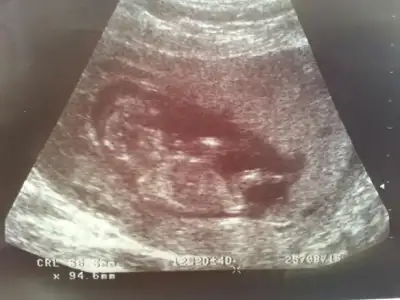

Kizlar bnm bebisimede bakarmisinz rica etsem,doktor 16.haftayibekle dedi,biz 13. Haftadayiz..

Tsk ederm cnm,bunda yanilma payi olmuyor degil mi?bariz belli kız olduğu. nub yan yatmış

o gördüğümüz nub ise açılı sanırım erkekKizlar bnm bebisimede bakarmisinz rica etsem,doktor 16.haftayibekle dedi,biz 13. Haftadayiz..

Cnm bu en son foto 13+6, bunada baksana daha net bu foto..Canım ilk fotografa bakmamıştım bebek tam yan değil hafif arkası dönük sidellanın tahmini doğru sanırım...